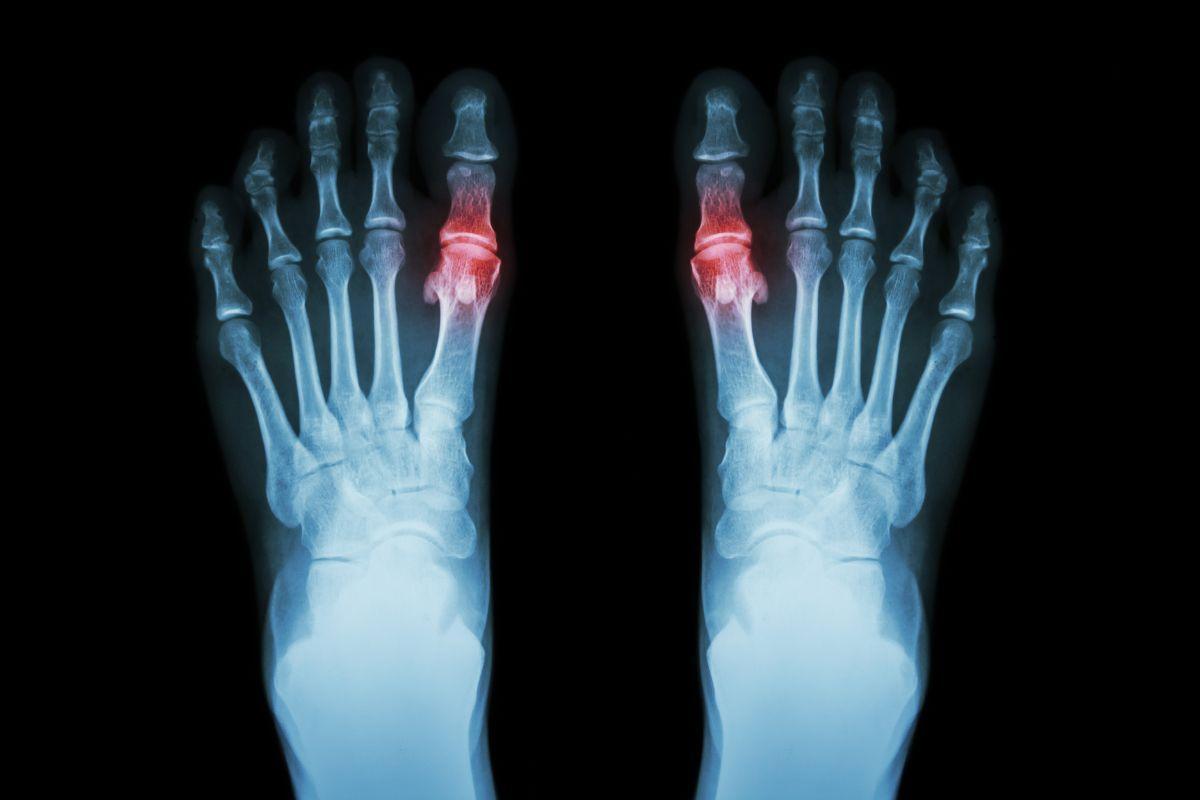

โรคเกาต์ เป็นโรคข้ออักเสบเฉียบพลันที่พบได้บ่อยในทุกเพศทุกวัยเกิดจาก กรดยูริก ในเลือดสูงลักษณะเด่นของโรคคืออาการปวด บวม แดง ร้อนบริเวณข้อต่อ โดยมักเกิดขึ้นที่โคนนิ้วหัวแม่เท้าอย่างรุนแรงจนตื่นกลางดึก ราวกับถูกไฟช๊อต ระดับความรุนแรงของอาการมีตั้งแต่ รุนแรงน้อย ปานกลาง และรุนแรงมาก แต่สามารถควบคุมและป้องกันได้

• การตรวจภาพรังสี: แพทย์อาจสั่งตรวจเอกซเรย์ข้อที่มีอาการเพื่อหาสาเหตุอื่นๆ ของการอักเสบ เช่น โรคข้ออักเสบรูมาตอยด์ โรคข้อเสื่อม